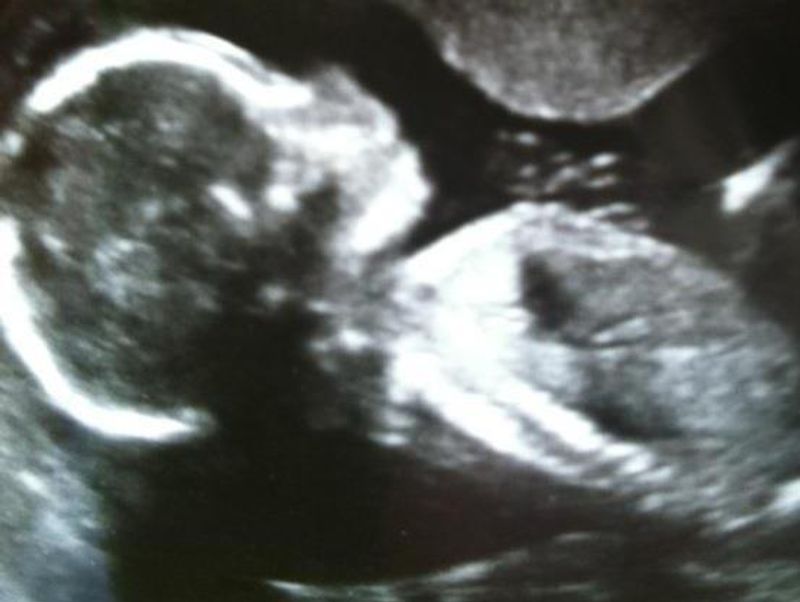

The definition of matrescence is simply the process of becoming a mother. It's the social, psychological, emotional and physical affects a woman goes through to become a mother.

From girl to woman, from woman to mother, matrescence is the essence of transition. This project was made in dedication to both the mothers you see in these images, and the mothers who aren't. It's for every girl that became a woman, and transformed into a mother.

The project explores matrescence through archive images of mothers when they were just girls. Before they were given the responsibility of new life. There's metaphorical imagery, to translate the process of matrescence as its not often something to be seen, but is instead quietly felt. There's also intimate portraits, of mothers and their children, taken by both myself and the mothers and children themselves. This project was a collaboration with mothers for mothers.